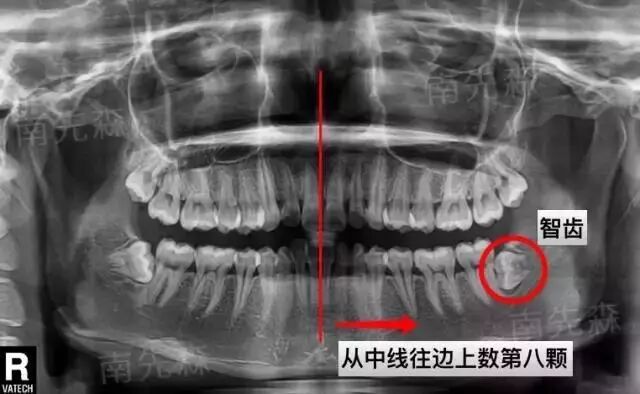

02.拍牙片

看不见的不等于不存在,也有可能是埋伏了。

看牙片就能清晰看到有没有智齿,智齿长的位置怎么样,要不要拔,一切清晰明了

以上是阻生智齿